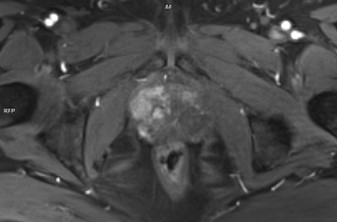

Figura 1: T2 axial si sagital

Discuţie caz nr 80: Pacientul cu suspiciune biochimică de neoplasm prostatic PSA 9.3 ng/ml efectuează examinare IRM multiparametrică și se pune în evidență anterior, la nivelul zonei prostatice superficiale drepte, cu dezvoltare în treimea inferioară şi treimea medie, o leziune de 1.9 cm în hiposemnal T1 cu restricție de difuzie a apei și priză de contrast în timp precoce; dacă acest pacient nu efectua această examinare și medicul urolog făcea puncție biopsie prostatică „în orb” foarte probabil nu se ajungea la diagnostic datorită poziționării anterioare a leziunii.

IRM multiparametric al prostatei este evaluarea inițială a bărbaților fără biopsie cu suspiciune clinică de cancer de prostată. Clasificarea PI-RADS este un sistem pentru raportarea IRM de prostată care își propune să standardizeze tehnica și interpretarea între centre. Leziunile PI-RADS 4 si 5 ridică o suspiciune clinică mare de cancer de prostată şi permite țintirea exactă a locului de punctie-biopsie pentru diagnostic.

DE LUAT ACASĂ!!! Examinarea IRM multiparametrică de prostată ajută medicul urolog la diagnostic prin indicarea leziunilor la nivelul cărora să facă biopsie țintită. Examinarea la aparate cu magnet 3 Tesla este mai sensibilă și se recomandă că examinarea să conțină și achiziție 3D ponderată T2 cară să permită localizarea leziunii in timpul puncției.